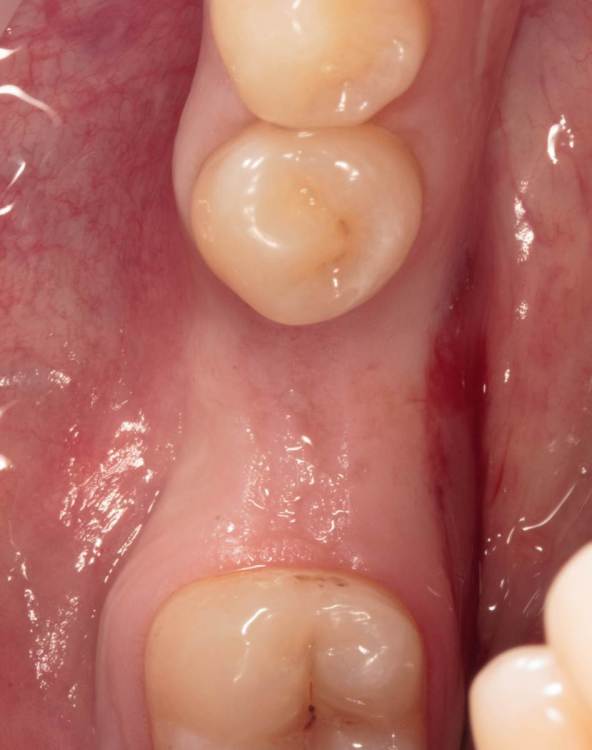

Женька Опубликовано 19 ноября, 2023 Автор Поделиться Опубликовано 19 ноября, 2023 (изменено) прошло 3 месяца. Изменено 19 ноября, 2023 пользователем Женька порядок фоток 1 Ссылка на комментарий

annda Опубликовано 23 ноября, 2023 Поделиться Опубликовано 23 ноября, 2023 Не жалуются на боли? Формик ниже края слизистой такое себе Ссылка на комментарий

Женька Опубликовано 23 ноября, 2023 Автор Поделиться Опубликовано 23 ноября, 2023 @annda неа, пока ни одной жалобы не услышал Ссылка на комментарий